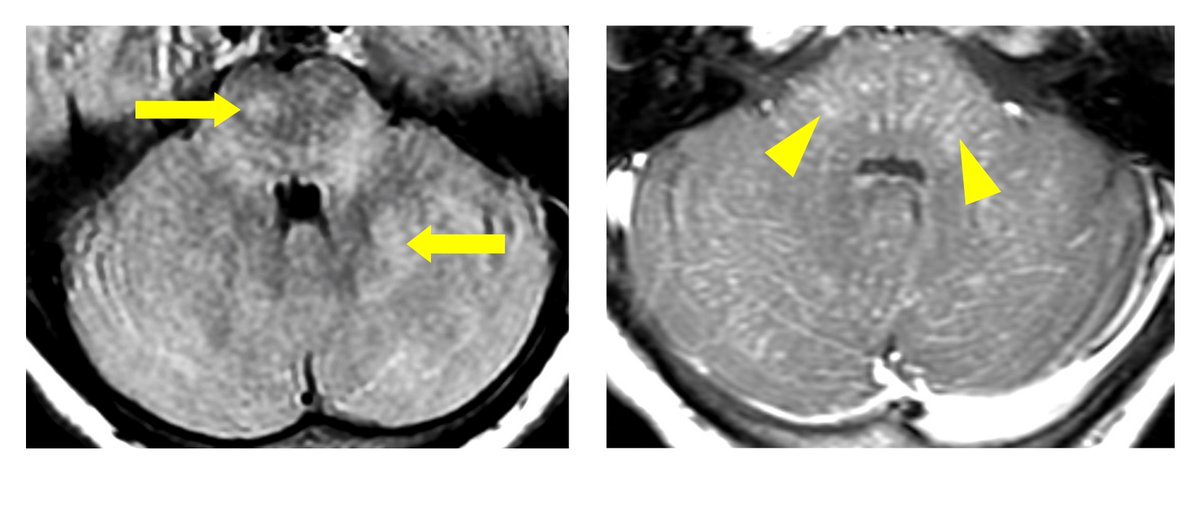

CLIPPERS should prompt neurologists to consider genes associated with familial hemophagocytic lymphohistiocytosis (HLH). UCC Medicine & Health Rebecca Boyd